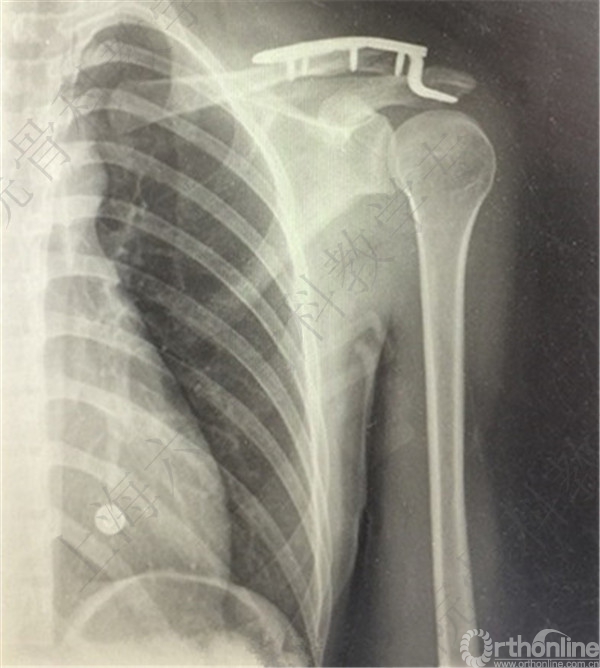

患者术后复查,X线摄片示:骨折端对位对线欠佳,远端骨块向前下方移位。

患者取出内固定,X线摄片示,骨折端畸形愈合,对位对线欠佳。